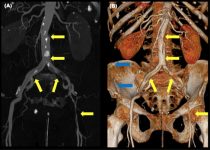

Внедрение в хирургическую практику новых технологий, в частности предоперационного компьютерного 3D-моделирования, позволяет выполнять сложнейшие реконструктивные органосохраняющие операции, которые еще совсем […]… далее